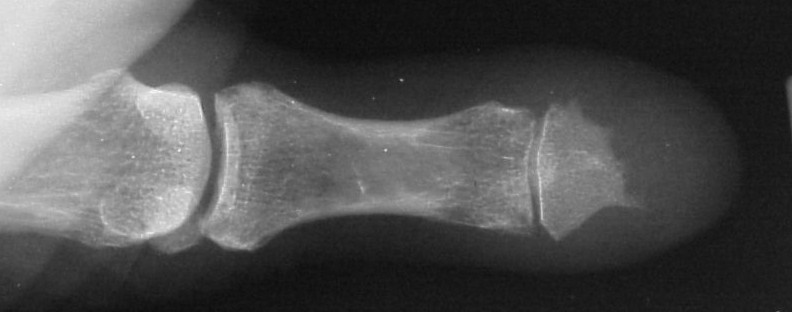

Comparison views of the opposite side:

Click for larger image